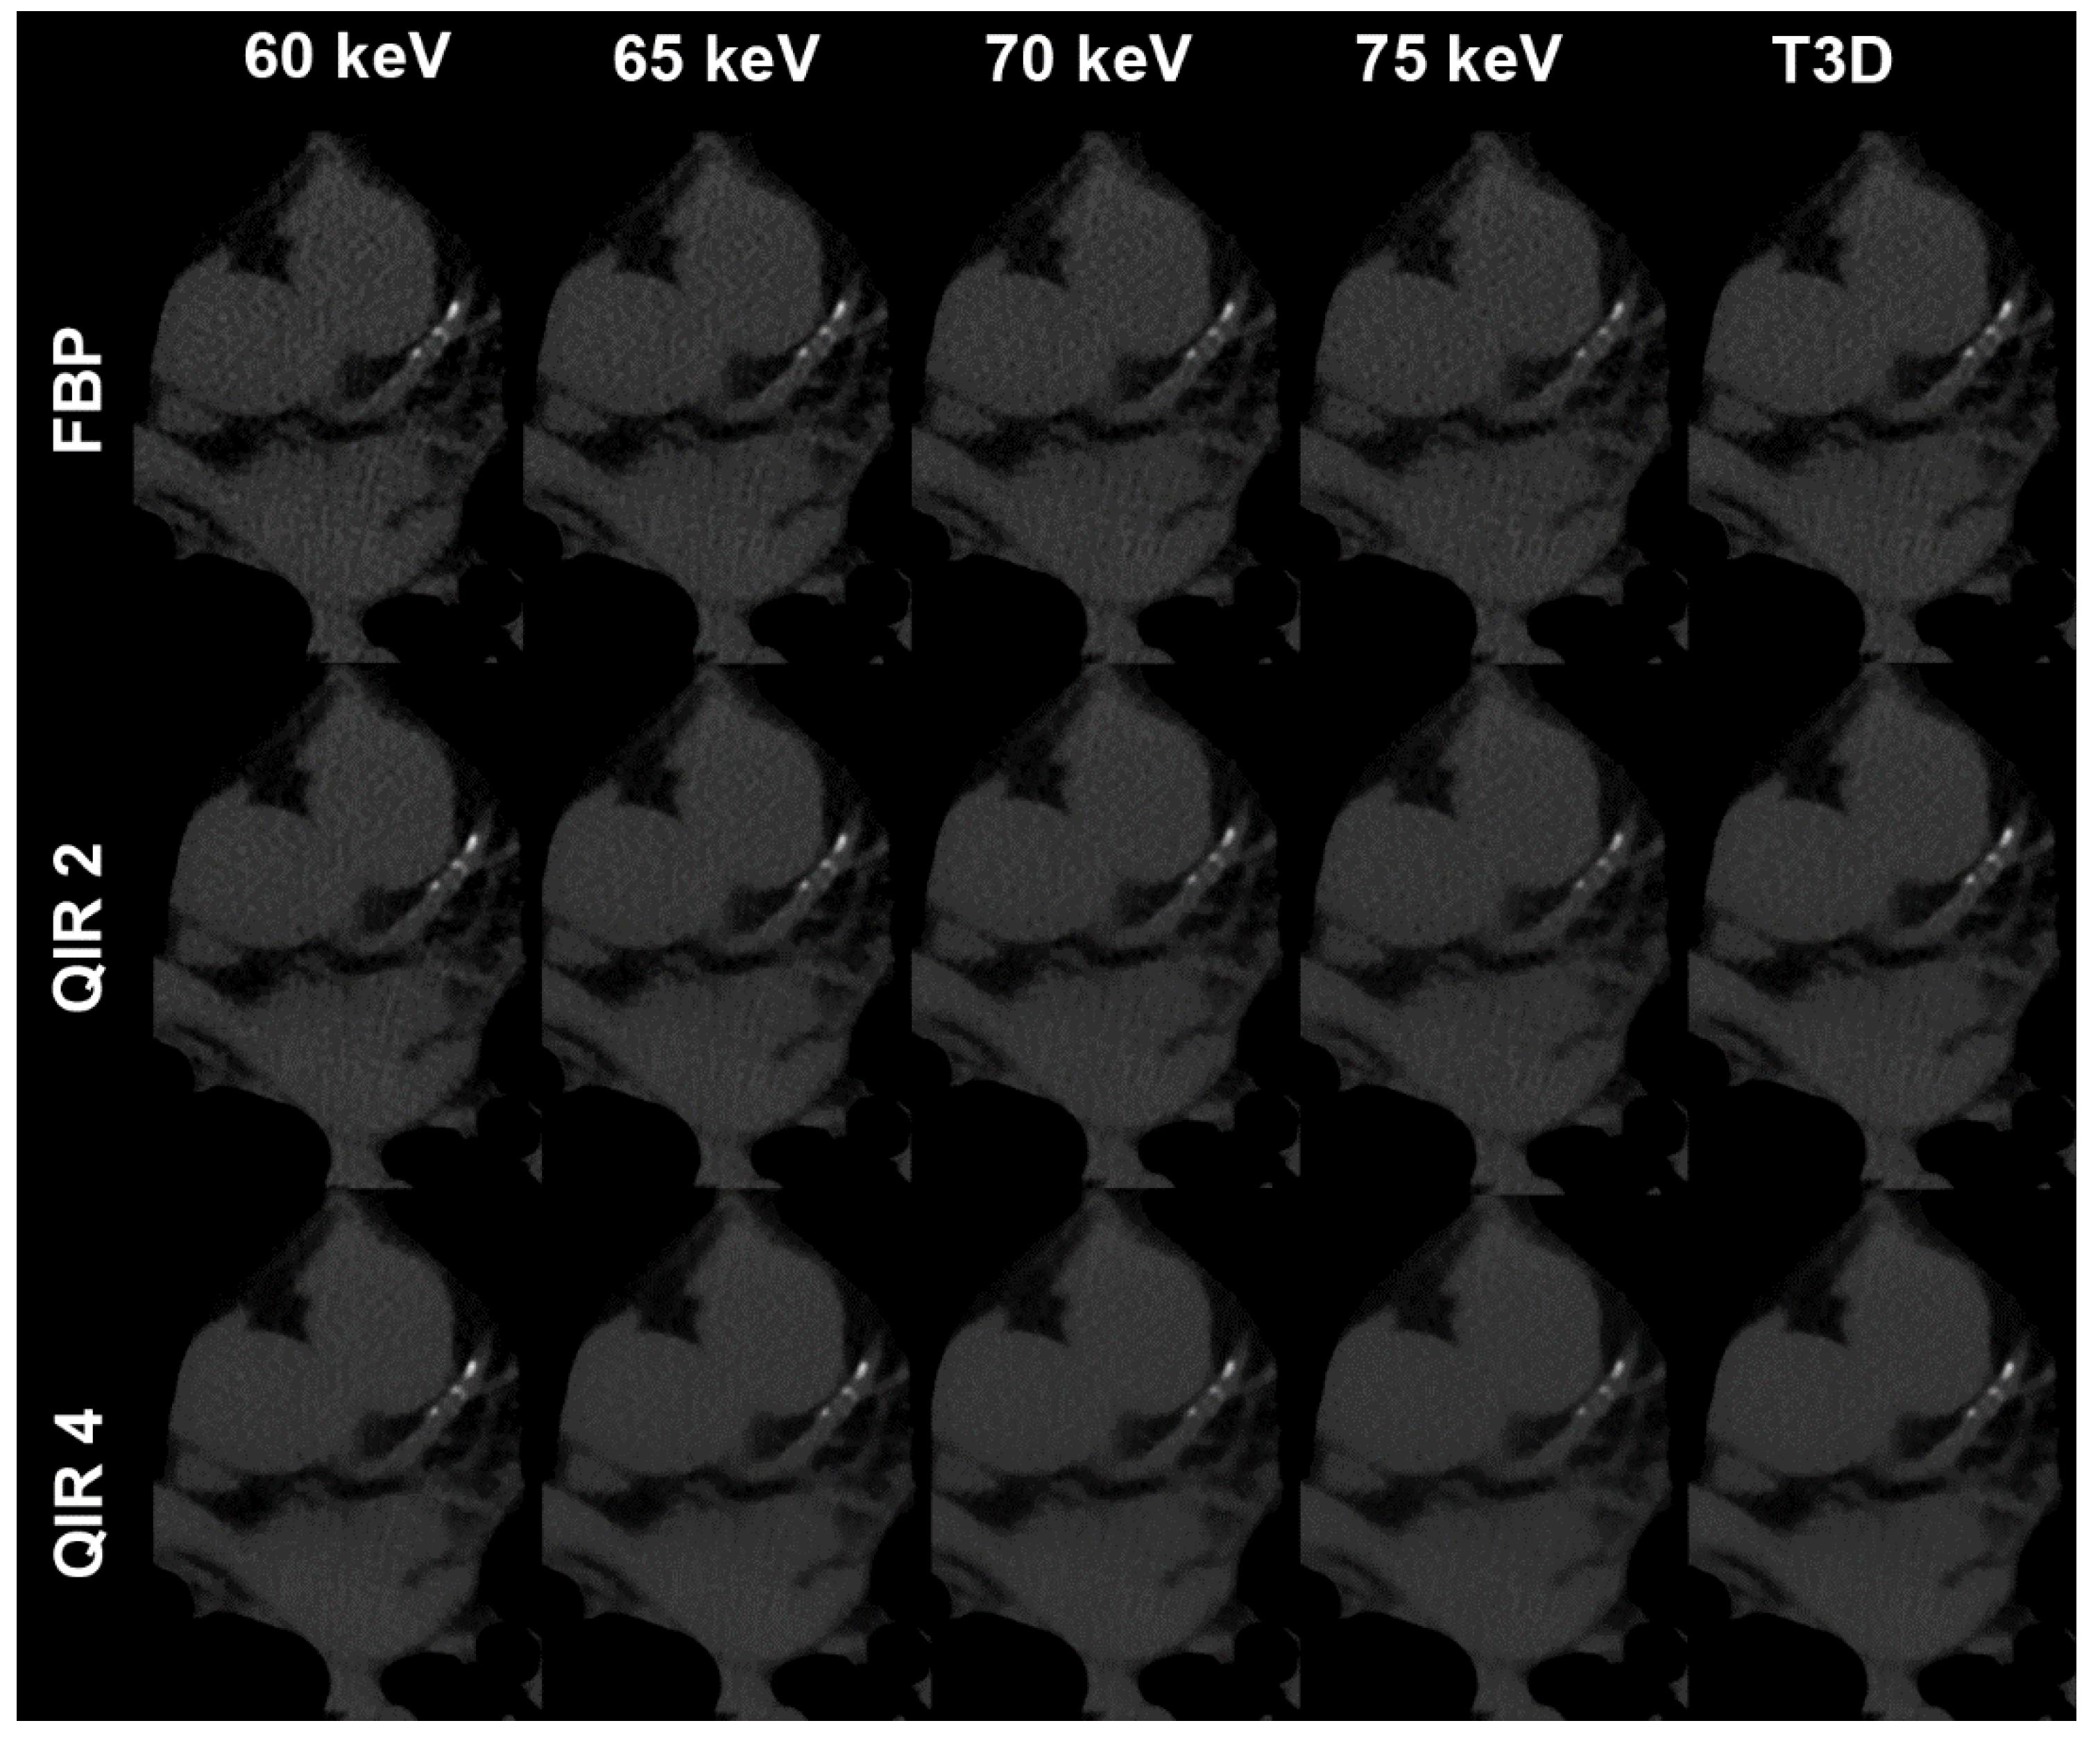

| VMI/T3D | FBP/no QIR | QIR 1 | QIR 2 | QIR 3 | QIR 4 |

|---|---|---|---|---|---|

| 60 keV | 107 (48–1060) | 100 (44–1026) | 91 (40–999) | 86 (36–974) | 80 (33–952) |

| 65 keV | 105 (44–1024) | 98 (40–989) | 90 (36–957) | 82 (33–930) | 74 (30–896) |

| 70 keV | 86 (38–978) | 76 (35–939) | 65 (31–886) | 64 (27–877) | 59 (24–850) |

| 75 keV | 64 (29–895) | 59 (26–867) | 56 (23–839) | 53 (21–819) | 49 (20–803) |

| T3D | 101 (46–1035) | 95 (43–1013) | 86 (39–981) | 80 (37–959) | 76 (34–934) |